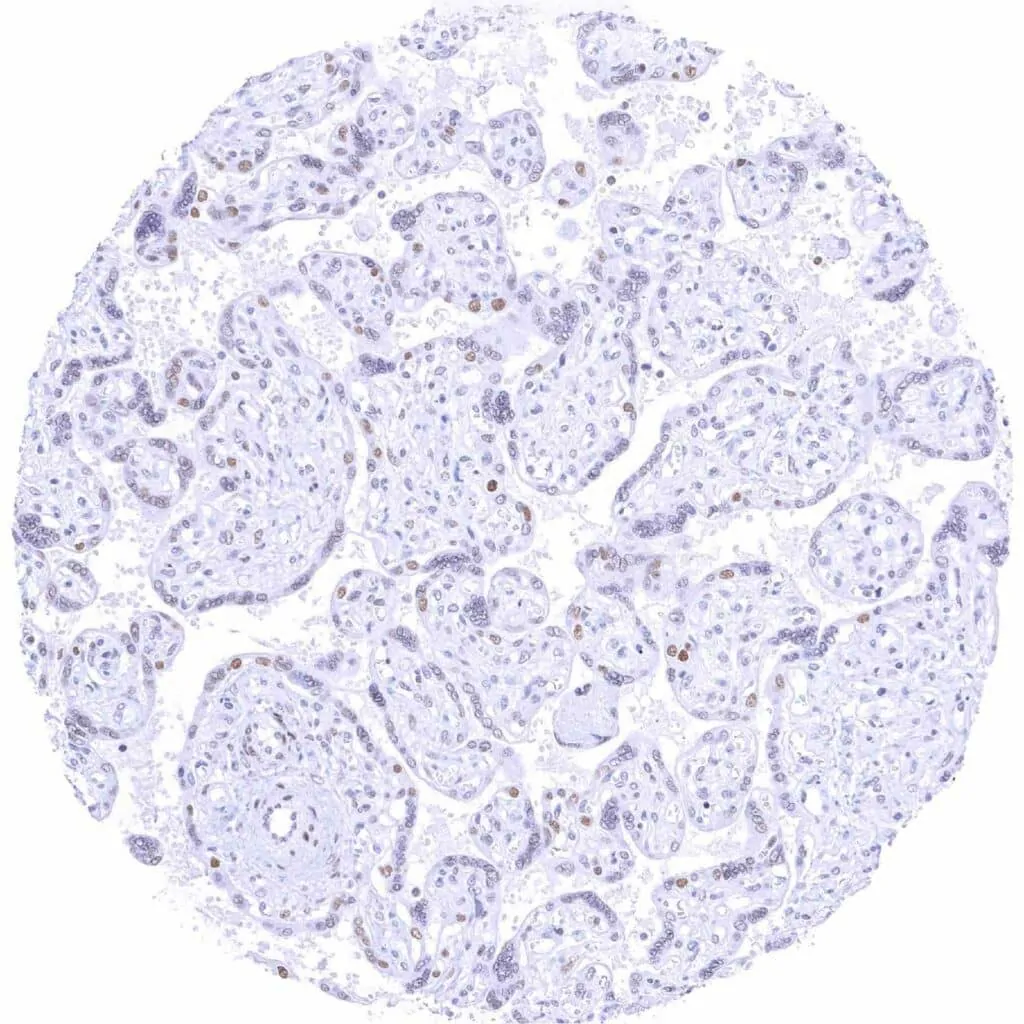

Placenta, early – Moderate to strong TLE1 staining of trophoblast and some stroma cells

Placenta, mature – TLE1 staining is weak to moderate in some stroma cells and in trophoblast cells